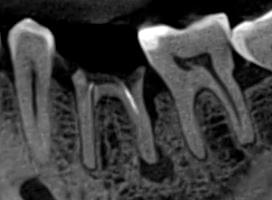

Ми розуміємо, наскільки важлива деталізація в ендодонтії та терапевтичному лікуванні.

Завдяки флагманському обладнанню PLANMECA, ми отримуємо знімки з мінімальним рівнем шумів та

високою роздільною здатністю, що дозволяє чітко візуалізувати морфологію кореневих каналів,

приховані каріозні порожнини та стан періапікальних тканин.